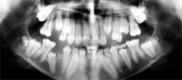

The hyperimmunoglobulin E syndrome (HIES) is a rare multi-system disease with non-immunological as well as immunological abnormalities. The syndrome is characterized by a triad of the most distinctive symptoms, such as pneumonia with pneumatocele formation, recurring staphylococcal skin abscesses and a high serum concentration of IgE. Central mediators of immune responses such as STAT1 and STAT3 affect immune responses and contribute to changes of the skin microbiome which subsequently can amplify the defective immune response against microbial and fungal pathogens. Reactions related to an environmental factor, such as sun-induced skin changes, in individuals during long-term medication therapy have also been reported. The dermatological symptoms, oral status and other health problems of a hyperimmunoglobulin E syndrome paediatric patient are presented. HIES is of great importance to different professionals because sufferers require special preventive and therapeutic management from early infancy in order to avoid complications which can even prove to be life-saving for such patients.